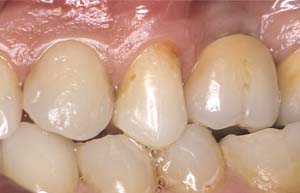

Second-stage surgery was performed after 4 months (Figure 8); healing abutments were placed and the soft tissue was allowed to heal for 5 more weeks. Then, splinted porcelain-fused-metal (PFM) crowns supported by custom gold abutments were delivered (Figure 9 and Figure 10).

Figure 9 Final implant-supported PFM restorations.